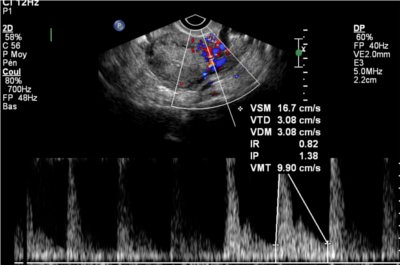

- les artères utérines